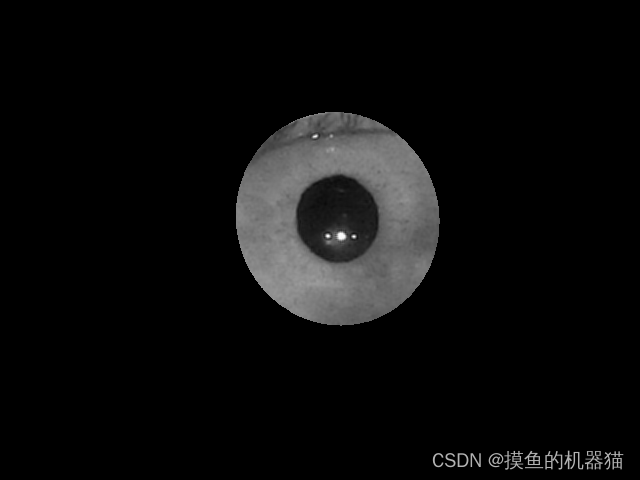

使用mask与原图进行与运算可以得到以下结果

根据连通域获取外接矩形,将虹膜区域裁剪出来得到以下图片